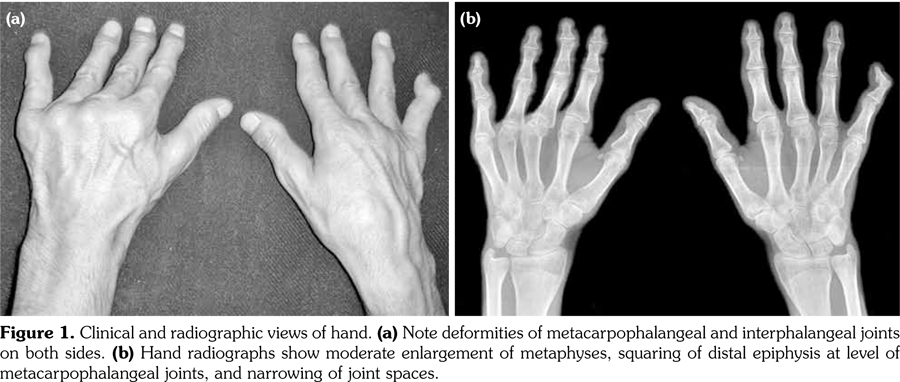

Physical examination revealed decreased range of motion in shoulders, wrists, metacarpophalangeal, proximal IP, distal IP, and ankle joints. In particular, the IP, metacarpophalangeal and metatarsophalangeal joints had bony enlargements, mild tenderness and flexion contractures; however, no signs of inflammation like redness, effusion, or other signs of synovitis (Figure1). The patient also had mild spinal scoliosis, significant thoracolumbar kyphosis, and pectus excavatum deformity. Furthermore, he had saddle nose deformity, bilateral floppy pinna and audiovestibular dysfunction (sensorineural hearing loss and tinnitus) (Figure 2). The rest of the systemic examination was unremarkable.

Radiographs of the hands showed enlargement of metaphyses, flattening of epiphyses, and narrowing of joint spaces with no erosions. Lateral radiograph of the foot revealed bilateral large ossified trigonum attached to the talus (mega os trigonum) (Figure 3). Radiographs of the spine showed increased kyphosis, generalized platyspondyly particularly at the thoracolumbar junction, and irregularity of the vertebral end- plates (Figure 4). Magnetic resonance imaging of thoracolumbar spine demonstrated irregularity in vertebral end-plates, multiple disk herniations, and platyspondyly (Figure 5). Dynamic contrast- enhanced magnetic resonance imaging of the wrist did not reveal any signs of synovial inflammation.

Clinical features of PPD have been described in several reports.(9-11) The radiographic features include varying degrees of epiphyseal involvement with enlargement of the epi-metaphyseal region, progressive joint narrowing, generalized platyspondyly, multiple intervertebral herniations, kyphoscoliosis, mega os trigonum and bone destruction with aging.(2,6,10) Our patient had progressive restriction of several joints, IP enlargements, dysplastic bone/cartilage changes, mega os trigonum and platyspondyly, with normal acute phase reactants. The presence of dysmorphic features and the absence of inflammatory signs should alert the physicians for the possible hereditary dysplasias like PPD.